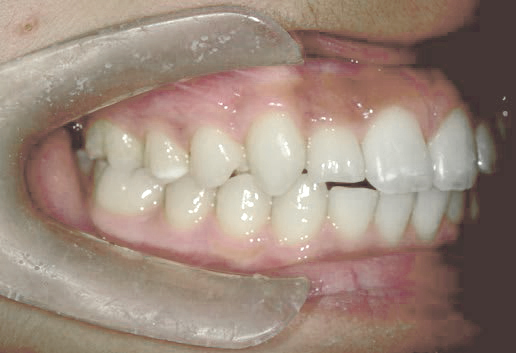

出っ歯

あごや骨格を正しく成長させる矯正治療

Aさん (矯正開始時:8歳)

Before

After

鼻がつまりやすく、口呼吸をしているために上あごが狭い状態でした。また上の前歯がかなり前へ傾いているため、お口をきちんと閉じていることができません。さらに、下の前歯もでこぼこしていました。

治療を終えて

装置によって上あごを拡大し、下あごを少し前へ成長させたことで、永久歯がきれいに並ぶスペースを確保しました。また、お口の機能が向上したことから鼻がよく通るようになり、口呼吸も改善され口も閉じやすくなったので顔の表情もよくなりました。

主訴・治療内容 下あごが後ろに下がり、出っ歯のようになっていることを心配して、無料相談に来院されました。

治療期間 2年半

費用 462,000円(税込)